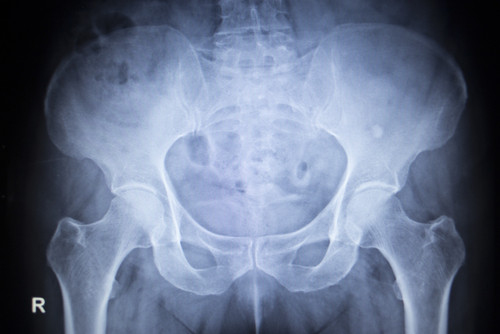

Geen bewijs voor celecoxib bij artrose

Celecoxib wordt niet veel voorgeschreven door huisartsen. Meerdere NHG-Standaarden benoemen dat er weinig bewijs is om dit middel boven andere NSAID’s te verkiezen. Patiënten komen echter wel regelmatig bij de huisarts voor een herhalingsrecept celecoxib, dat de specialist hun heeft voorgeschreven…